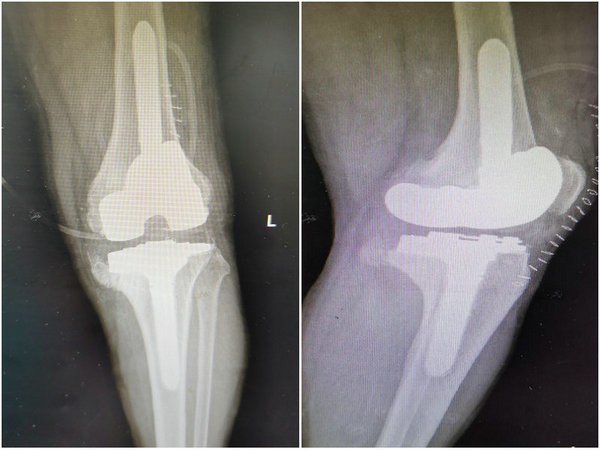

患者术后X线片